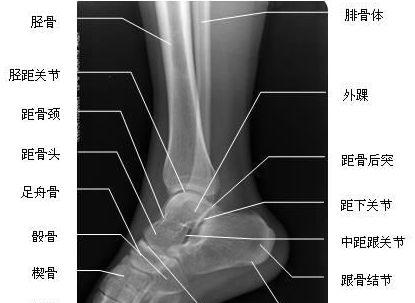

距骨:分为头,颈,体三部分,与足舟骨,跟骨,胫骨和腓骨形成关节.

【工作必备】x线解剖图谱 系统解剖(骨骼篇),非常全面,强烈建议收藏